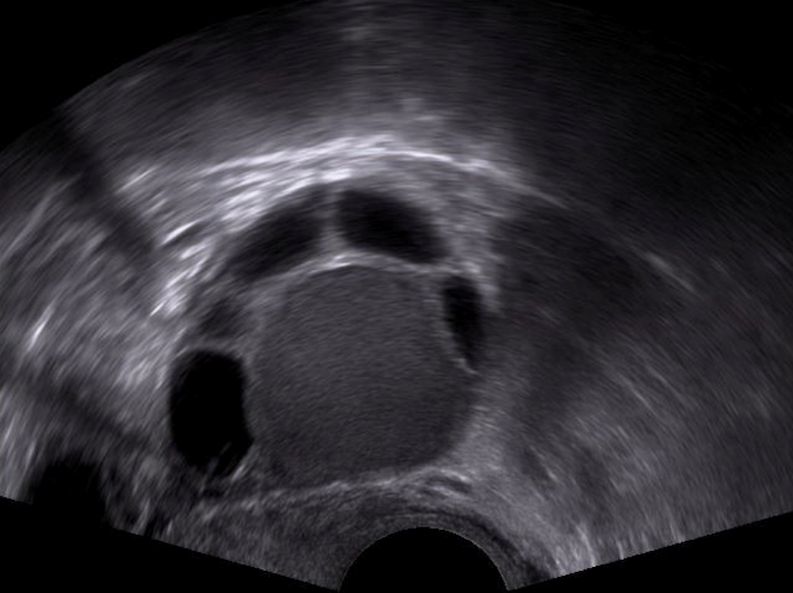

Etwa 10–15 % aller Frauen im gebärfähigen Alter (also zwischen Pubertät und Menopause) sind von Endometriose betroffen. Patientinnen mit Endometriose leiden oft unter einer Vielzahl belastender Symptome. Am häufigsten leiden diese Patientinnen unter starken Regelschmerzen, aber auch unter chronischen Unterbauchschmerzen, Schmerzen beim Geschlechtsverkehr, Verdauungs- oder Blasenproblemen, unerfülltem Kinderwunsch, Erschöpfung sowie psychischen und sozialen Belastungen. Bis heute ist nicht vollständig geklärt, wie und warum Endometriose entsteht. Es gibt verschiedene Theorien (z. B. retrograde Menstruation, genetische Faktoren, Immunabwehr-Störungen), aber keine endgültige Erklärung. Ohne dieses Wissen ist gezielte Prävention, Diagnostik und eine kausale Therapie nur eingeschränkt möglich. Es werden verschiedene Formen der Endometriose unterschieden: peritoneale Endometriose (Bauchfell), ovarielle Endometriose (Eierstöcke/Endometriome), Adenomyose (Endometriose in der Gebärmutterwand) und tief infiltrierende Endometriose (z.B. in Darm oder Blase).

Einer unserer Forschungsschwerpunkte liegt auf Untersuchungen des Mikroenvironments dieser verschiedenen Endometriose-Entitäten mittels Spatial Multiplex Imaging. Ziel ist die genaue Analyse der Gewebe-Zusammensetzung bzgl. Immunologie, Inflammation und Angiogenese, um darüber möglicherweise eine schnellere und sicherere Diagnosestellung